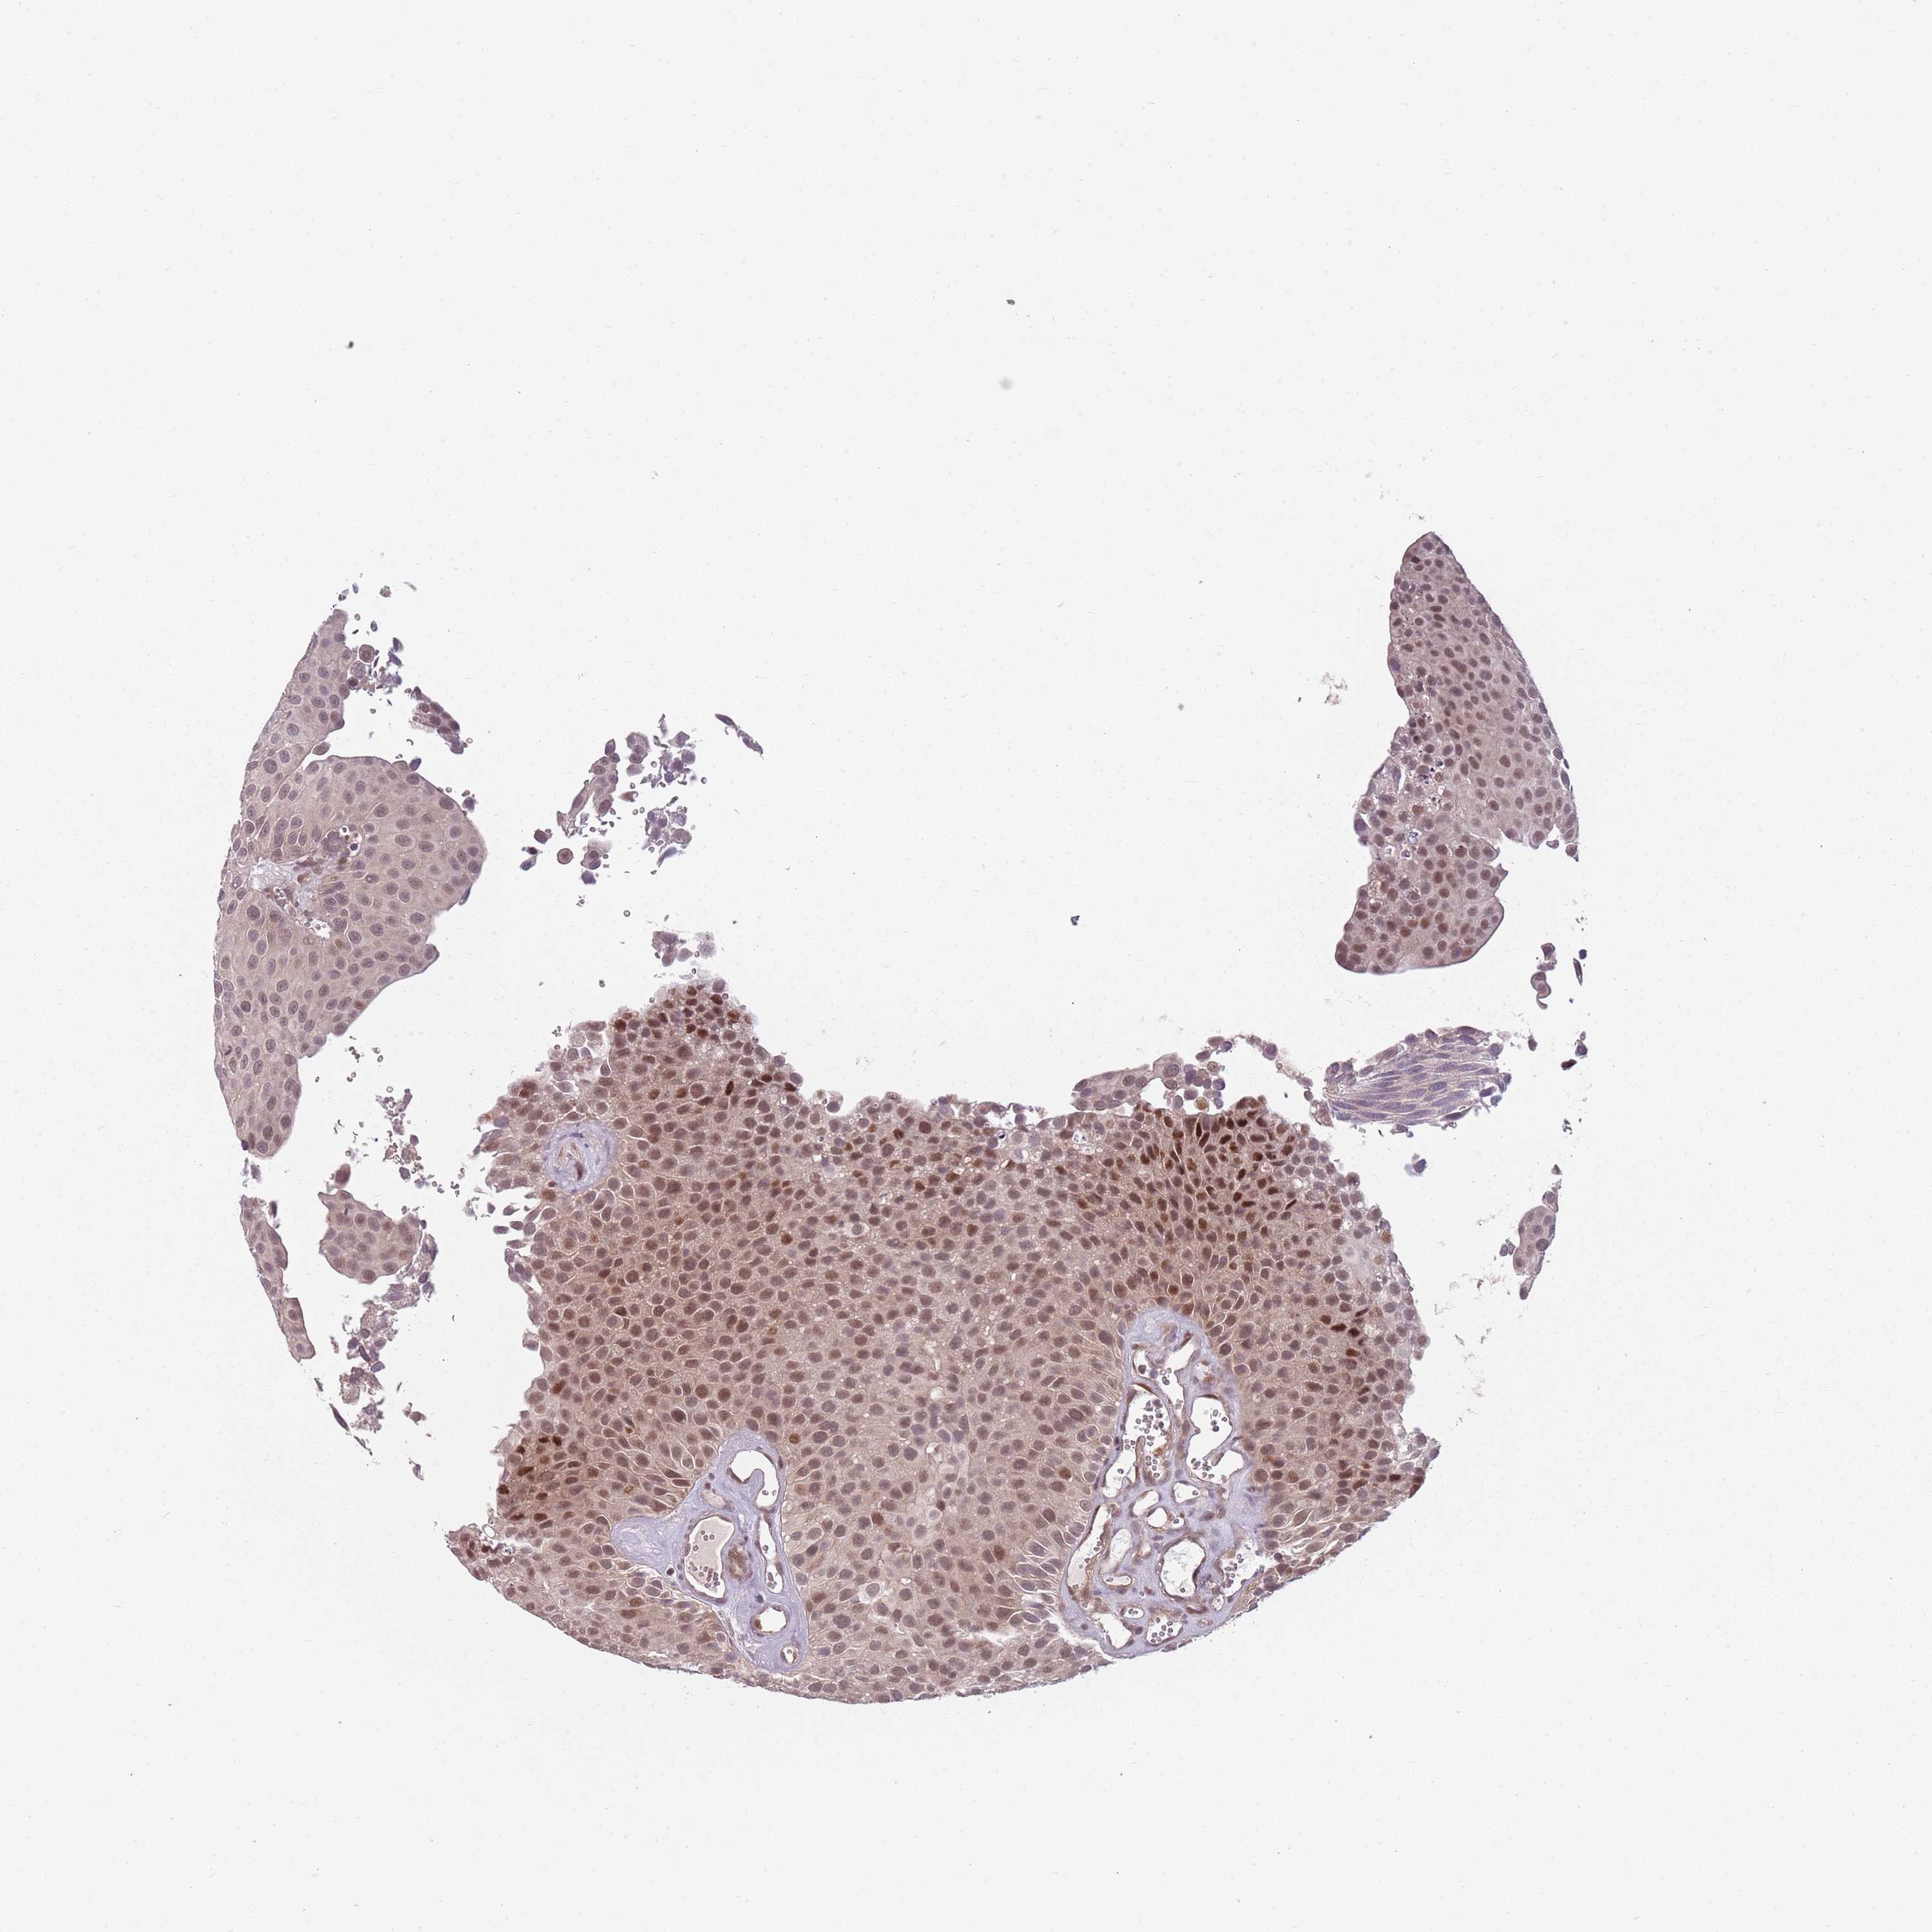

UROTHELIAL CANCER - Protein expressioni

A mouse-over function shows sample information and annotation data. Click on an image to view it in a full screen mode. Samples can be filtered based on level of antibody staining by selecting one or several of the following categories: high, medium, low and not detected. The assay and annotation is described here.

Note that samples used for immunohistochemistry by the Human Protein Atlas do not correspond to samples in the TCGA dataset.

Antibody stainingi

Antibody staining in the annotated cell types in the current human tissue is reported as not detected, low, medium, or high, based on conventional immunohistochemistry profiling in selected tissues. This score is based on the combination of the staining intensity and fraction of stained cells.

Each image is clickable and will lead to virtual microscopy that enables deeper exploration of all samples and also displays staining intensity scores, fraction scores and subcellular localization as well as patient and tissue information for each sample.

Antibody HPA046065

Staining

High

Medium

Low

Not detected

Intensity

Strong

Moderate

Weak

Negative

Quantity

>75%

75%-25%

<25%

None

Location

Nuclear

Cytoplasmic/membranous

Cytoplasmic/membranous,nuclear

Urothelial carcinoma, High grade

Urothelial carcinoma, Low grade